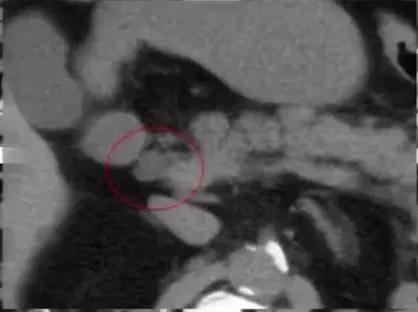

图1:腹膜后方下腔静脉处于腹主动脉左侧;左肾静脉出左肾门后,汇入下腔静脉路径缩短

图2:冠状位重建显示下腔静脉肝段和肝下段缺如,向上直接延续为奇静脉